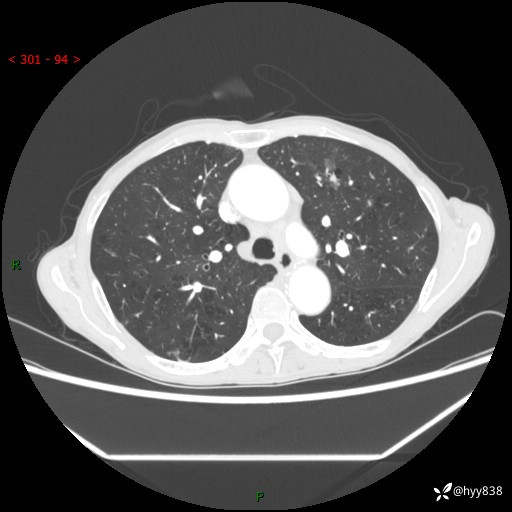

69岁/女,发现肺占位3天余。精彩好病例,请慧诊---(有结果)

【患者信息】:69岁/女

【主诉】:发现肺占位3天余

【现病史及既往史】:患者3天余前因既往肺气肿复查胸部CT发现“右肺下叶结节、双肺多发结节、双肺门及纵膈淋巴结增大”,平素偶有咳白色粘液痰,下肢乏力,无明显低热、盗汗、咯血、胸痛、喘气等不适,今为求明显结节性质遂来我院门诊就诊,门诊以“孤立性肺结节”收治入院。 起病以来,患者精神饮食睡眠一般,大小便正常,体力无明细变化,体重近年来较前下降。

【检查】:胸部CT增强